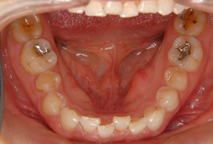

中・高校生(歯のデコボコ) 13歳

治療前(抜歯ナシ)

治療後(期間:約1年6ヶ月~2年)

①主訴:八重歯を治したい

②診断名あるいは主な症状:前歯部叢生

③年齢:13歳

④治療に用いた主な装置:マルチブラケット装置

⑤抜歯部位:写真の症例は非抜歯(かみ合わせや叢生の程度により抜歯が必要となる場合もある)

⑥治療期間:1年半~2年半

⑦治療費:検査:49,500円

基本矯正費用:880,000円~

調整料:6,600円(ひと月に1回)

⑧リスクと副作用:治療開始後数日は噛むときに痛みがあります。

虫歯や歯肉炎予防のために毎日の適切な歯磨きが重要。

装置が破損する場合があり、その時は連絡が必要

治療後には後戻り防止として保定装置が必要

歯の移動により歯根の先が溶ける場合がまれにある。